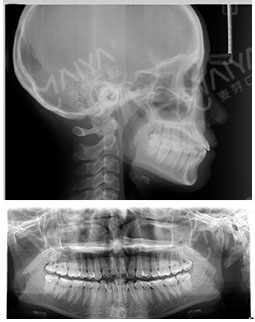

经过朋友良心推荐,最终选择了麦芽口腔。在麦芽是张超主任给我检查的牙齿,然后跟着医助拍的片,这期间都有专人负责,张主任很专业的为我定制了方案,当天就取了牙模~

在主任的建议下拔了牙,根据我的牙齿情况,主任做了适合我的矫牙方案。选择了时代天使双膜矫治器,矫治器是透明的,可以自行摘戴,满足了我想矫正又怕丑的要求,让我在别人不知道的情况下,拥有整齐的牙齿,在矫正之前是可以在计算机上模拟显示整个矫治过程中牙齿的变化过程,可以很直观的看到,让我自己感觉心里很放心,经过一个月的等待,终于戴上了牙套,给主任和麦芽点赞!